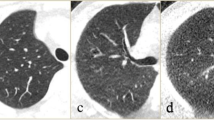

Images were reconstructed with 512 × 512 matrix, 2 mm slice thickness with 1 mm slice interval. Cyst scores (% of lung volume affected by cysts) were quantified by semi-automated software (Lung Density Analysis, Canon Medical) (Fig. 1). Signal-to-noise ratio (SNR) was calculated for each reconstruction. Data was analyzed by linear correlation, paired t-test, and Bland–Altman plots.

Chest CT of a 29-year-old female with LAM. A Standard scan with AIDR3D. B Standard scan with low attenuation areas highlighted in red. Radiation dose 1.90 mSv and cyst score 16.8%. C SilverBeam scan with AiCE. D SilverBeam scan with low attenuation areas highlighted in red. Radiation dose 0.33 mSv and cyst score 15.9%